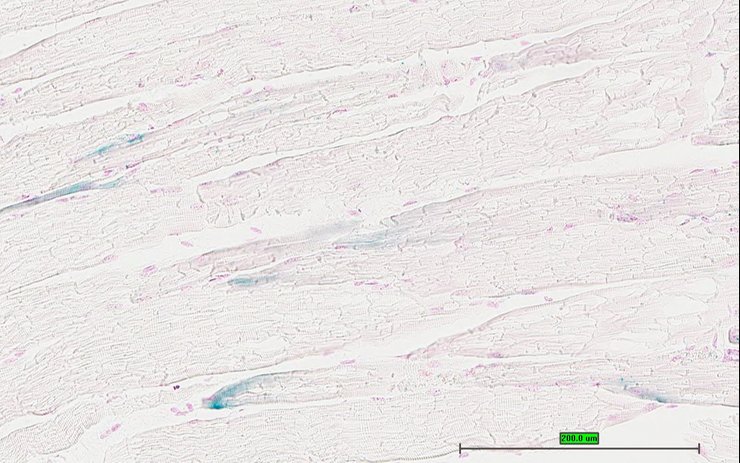

Specimen UC Davis_1873112: postnatal adult; Cox15tm1.1(KOMP)Vlcg/Cox15+ (more )

Structure Level Pattern Image Note

TS28: quadriceps femoris muscle Present UC Davis_1873112

Specimen UC Davis_1873113: postnatal adult; Cox15tm1.1(KOMP)Vlcg/Cox15+ (more )

TS28: quadriceps femoris muscle Present UC Davis_1873113

Specimen UC Davis_1873114: postnatal adult; Cox15tm1.1(KOMP)Vlcg/Cox15+ (more )

TS28: quadriceps femoris muscle Present UC Davis_1873114